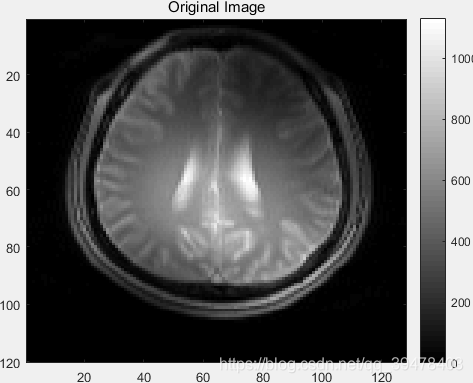

1. 加载全采样 MR 图像并显示

brainCoils 是 5 通道的大脑 MR 图像,分别来自 Nc = 5 个线圈各自的 全采样 结果,每张图像 size = 120 ×128,type = double

originalImage = rsos(brainCoils); % 120×128 double

imagesc(originalImage);

title('Original Image');